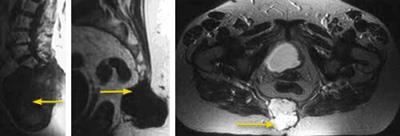

MRI scans showing chordomas

(Left) The same chordoma in the sacrum as it appears in an MRI scan taken from the side. (Center) How the chordoma appears in a cross-sectional MRI scan of the base of the spine and (right) of the entire pelvis.